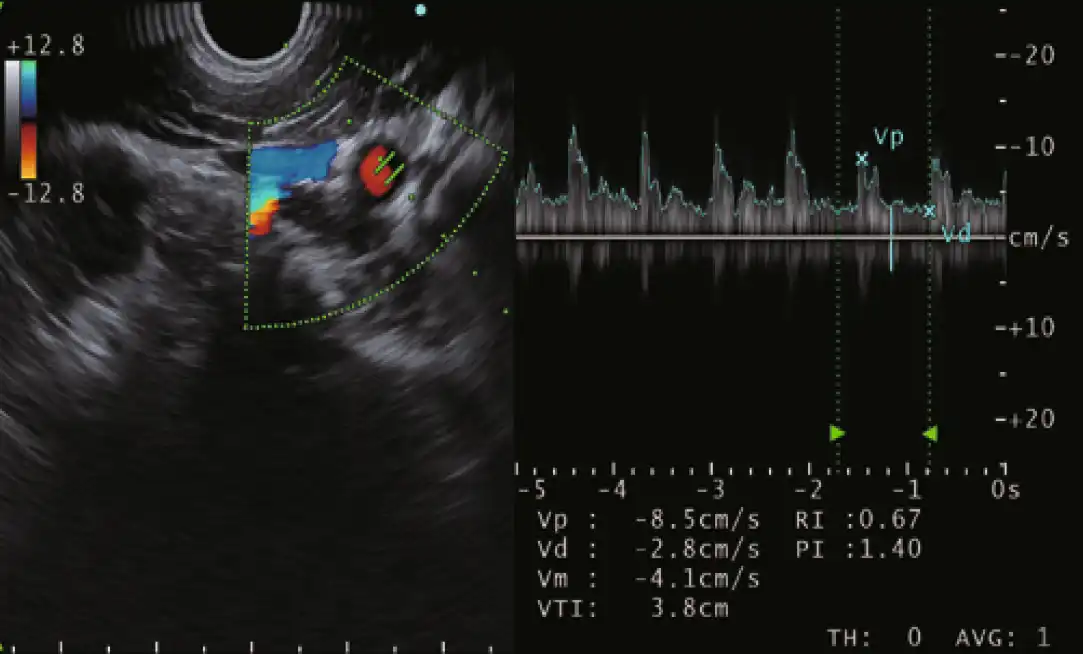

多普勒模式

EU-ME3 提供三种基本的多普勒模式,以更清楚地分辨血流--彩色血流、能量血流和脉冲波多普勒(PWD)。多普勒模式可用于支持更安全的手术,使病人和医生都受益。

除了三种基本的多普勒模式外,EU-ME3还具有H-Flow模式。H-Flow是一种更敏感的多普勒模式,可显示定向血流,且花纹较少。它对回声内窥镜尖端周围的小血管成像特别有用。

彩色流 能量流

脉冲波多普勒 H-Flow